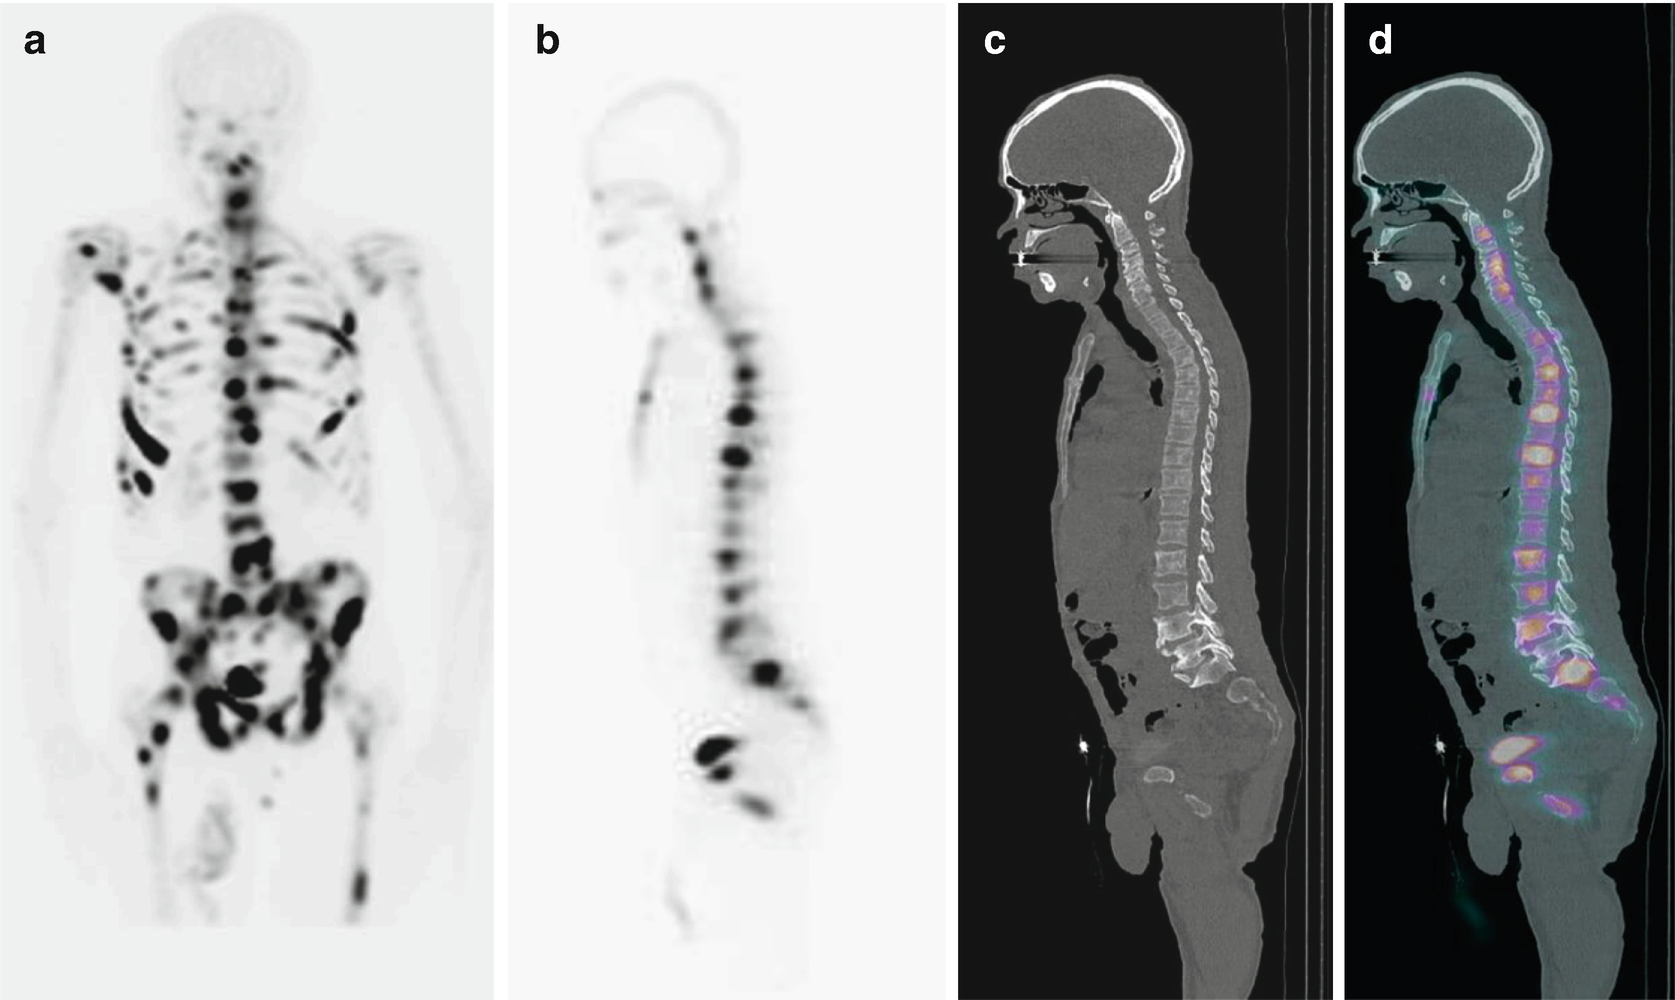

View Nm Bone Scan Whole Body With Spect Images. A bone scan is a nuclear imaging procedure. A bone scan can't always tell what's causing unusual spots in your bones.

If an area needs further study, a spect scan is performed using a gamma camera that rotates around the body. A bone scan or bone scintigraphy /sɪnˈtɪɡrəfi/ is a nuclear medicine imaging technique of the bone. Learn about bone scan with free interactive flashcards. The algorithm successfully segmented vertebrae in the thoracolumbar spine.